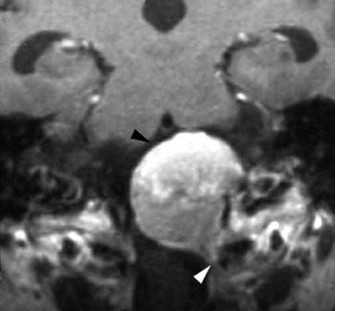

(а) MPT, Т2* GRE, аксиальный срез: определяются участки «выцветания» изображения, соответствующие участкам кальцификации гирального характера.

(б) Постконтратсное Т1-ВИ, режим подавления сигнала от жира, аксиальный срез: определяется контрастное усиление объемного образования серпантинного, гирального характера.

Других областей поражения или кожных аномалий выявлено не было. На данных снимках представлен случай предполагаемого (хирургически не подтвержденного) менингоангиоматоза.